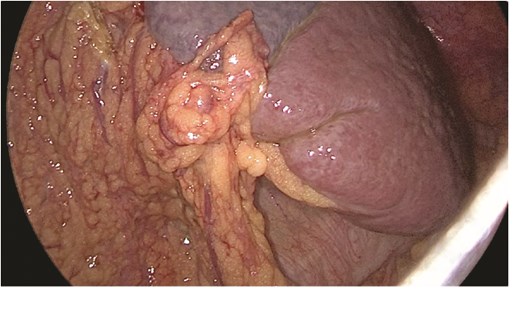

Multidisciplinary discussion was held to evaluate the most appropriate course of action for the patent condition, and the consensus was reached to pursue embolization as a first intervention. Embolization was performed by interventional radiology with no complications post-procedure, and the patient was optimized prior to her procedure. Patient was taken to the operating room in stable conditions. The spleen was enlarged around 20 cm. Inferiorly, the omentum and part of the transverse colon was attached to the spleen (Fig. 3), so we freed the omentum from the splenic tissue. The dissection continued until reaching short gastric vessels and entering the lesser sac (Fig. 4). Once the lesser sac was entered, the splenic vessels were identified (Figs 5 and 6), the splenic vein was hugely dilated with multiple collateral branching vessels at the hilum. Gaining posterior mobilization of the vein was challenging. The splenic artery was tortuous from the insertion around itself (Fig. 7). After complete mobilization of the fundus, we elected to divide each vessel starting with the splenic artery so we can achieve full mobilization of the vein (Fig. 9). After controlling the splenic artery, the splenic vein was dissected proximal to the splenic hilum (Fig. 8). It was hugely dilated and its wall is thickened secondary to AV fistula. It was difficult to achieve circumferential dissection, so we decided at that moment to convert to laparotomy to complete ligating the vein and to retrieve the specimen (Fig. 10a and b).

The spleen inferiorly, attached to it the mesentery and the transverse colon.